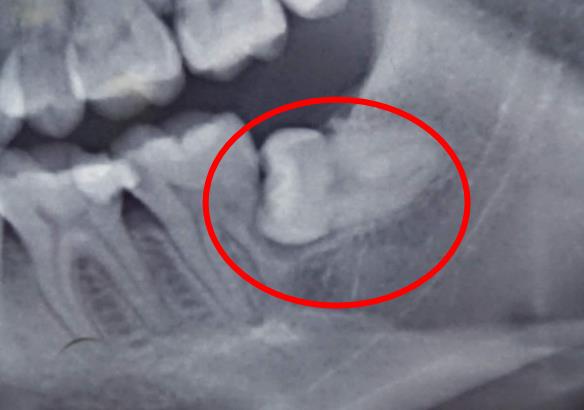

被智齒擠壞的鄰牙(第二磨牙)是很無辜的,但是沒辦法,鄰居不好當,一不小心就成了替死鬼。不過是不是壞掉的鄰牙都建議拔除呢?不見得。可以根據鄰牙的實際情況來確定。

如果鄰牙壞得嚴(yan) 重或者是智齒嵌入進去了,沒法單純拔除鄰牙或者是智齒,可能鄰牙和智齒都需要一起拔除了,這顆鄰牙就可惜了。

如果鄰牙齲壞不是很嚴(yan) 重,而且可以單獨拔除智齒,並在拔除智齒後還能對鄰牙進行補牙,這種當然是非常理想的結局了。